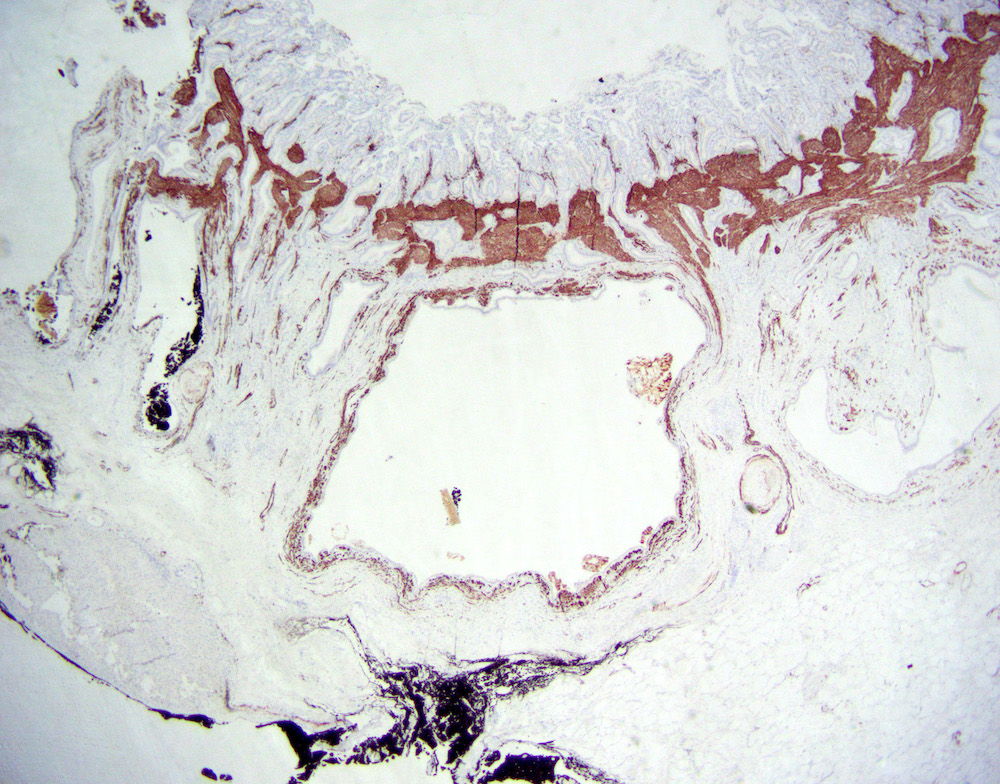

Microscopic (histologic) description

- Cystically dilated benign biliary glands accompanied by smooth muscle hypertrophy of gallbladder wall, thickened / fibrotic subserosa (StatPearls: Adenomyomatosis [Accessed 26 January 2021])

- Glands are distinct from the Rokitansky-Aschoff sinuses, which are epithelial diverticula, usually multifocal and occur throughout gallbladder secondary to injury, versus adenomyomatous nodule (distinct localized lesion of the gallbladder wall, 1 - 1.5 cm mural nodule in the fundus) (Am J Surg Pathol 2020;44:1649)

- May have reactive epithelial changes, papillary change and intestinal metaplasia (StatPearls: Adenomyomatosis [Accessed 26 January 2021])

- Rarely, benign glands are seen in proximity to nerves, appearing as perineural and intraneural invasion only in the subserosal layer (benign gland-like structures may migrate into nerves due to chemotactic factors or signaling substances with activation of cell receptors) (Am J Surg Pathol 2007;31:1598)

- Adenomyomatous nodules may rarely show dysplastic / carcinomatous transformation, whereas dysplasia in Rokitansky-Aschoff sinuses appears to be more common; however, the true association between adenomyomatous nodules and neoplasia has not yet been determined (Am J Surg Pathol 2020;44:1649)

- Recently, papillary dysplastic lesions of adenomyomas have been identified (intracholecystic neoplasms of adenomyomas), demonstrating cystic and solid areas with papillary projections that show biliary, gastric and intestinal phenotypes, with low or high grade dysplasia (Am J Surg Pathol 2020;44:1649)

Microscopic (histologic) images

Contributed by Monica T. Garcia-Buitrago, M.D.